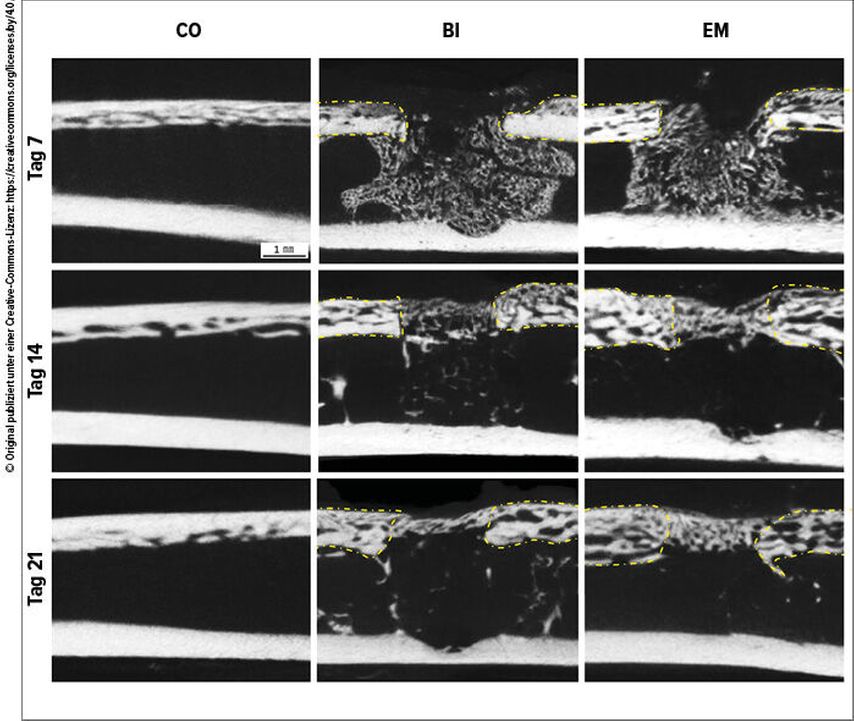

Eine weitere Untersuchung an Ratten belegt, dass ESM die Angiogenese sowie die Osteoblasten- und Osteoklastenaktivität signifikant steigert (p<0,05) und damit zur Verbesserung der Knochenheilung beiträgt (Abb. 3).11

Abb. 3: μCT-Auswertung der Knochenheilung nach Bohrlochverletzung. Gelb gestrichelte Linien markieren die Grenze zwischen bestehendem Knochen und Bohrlochdefekt (n=6). * p<0,05. CO: Kontrolle; BI: Knochenverletzung; EM: Supplementierung mit Eierschalenmembran (modifiziert nach Yashima N et al.)12